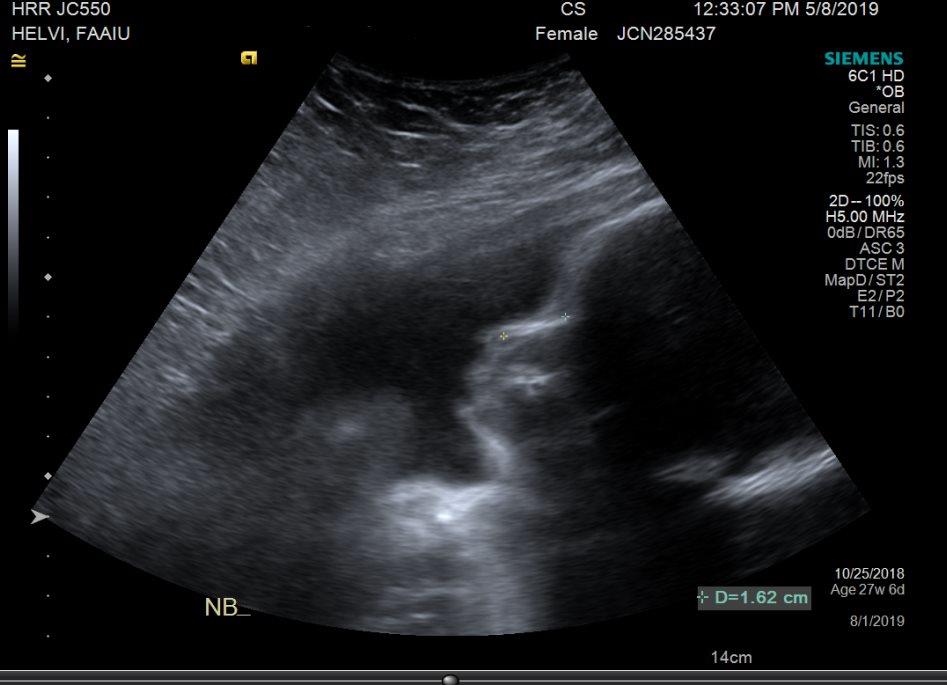

Thank you to everyone who has donated thus far! We are so overwhelmed by the outpouring of love & are so appreciative. So we just thought we’d update with a photo of our little one.